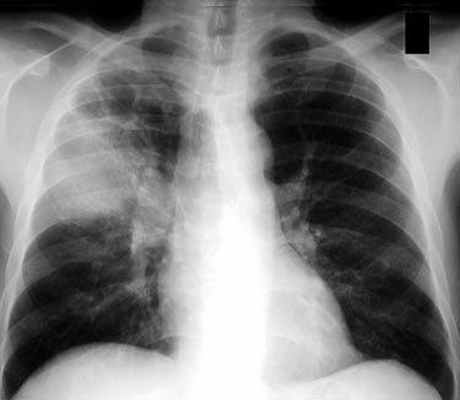

- Рентгенографию грудной клетки – на снимках появляются затемнения в местах поражения тканей;

Самым важным диагностическим исследованием является рентгенография грудной клетки.

Изменения на рентгенограмме (распространённость инфильтрации, наличие или отсутствие плеврального выпота, полости деструкции) характеризуют степень тяжести заболевания и служат основой в выборе антибактериальной противовоспалительной терапии. Рентгенография позволяет оценить динамику развития болезни и полноту выздоровления.

Диагноз «пневмония» устанавливается при наличии рентгенологически подтвержденной очаговой инфильтрации лёгочной ткани и, по крайней мере, двух из нижеперечисленных признаков:

- остро возникшей лихорадки (>38,0 °С);

- кашля с мокротой;

- физикальных признаков (фокус крепитации и/или мелкопузырчатые хрипы, бронхиальное дыхание, укорочение перкуторного звука);

- лейкоцитоза более 10х109/л и/или палочкоядерного сдвига (>10%).